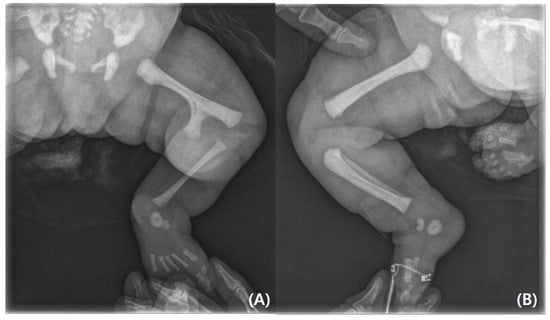

On physical examination, the infant’s left leg was shorter than the right leg, and her left foot had equinovarus (Figure 1). A large bony prominence was observed on the medial aspect of the left thigh. The left knee joint was unstable in all directions. The left fibula was palpable just lateral to the knee and ankle joints. The tibia, including the medial malleolus, was not palpable. The feet were grossly deformed because of equinovarus. Her upper extremities revealed contralateral tetradactylous ectodactyly, and the left side showed normal development with equal length and normal digits (Figure 2). A radiography examination of the lower extremities revealed the absence of the left tibia, a deformed left foot, and duplication of the distal left femur. No epiphyseal ossification was observed at the distal end of the left femur (Figure 3). Ultrasonography of the same leg confirmed weak quadriceps and undetectable patellar signals and additionally revealed a complete absence of any tibial anlage in the lower leg. Neurologically, the patient was intact, and on examination of her lower back, the gluteal cleft was midline with no dermatological anomalies on her lower back.

Figure 3. (A) Radiographs of lower limbs showing left distal femoral bifurcation, left tibial and patellar agenesis. (B) Normal femur, tibia, fibula, and patella on the right side.